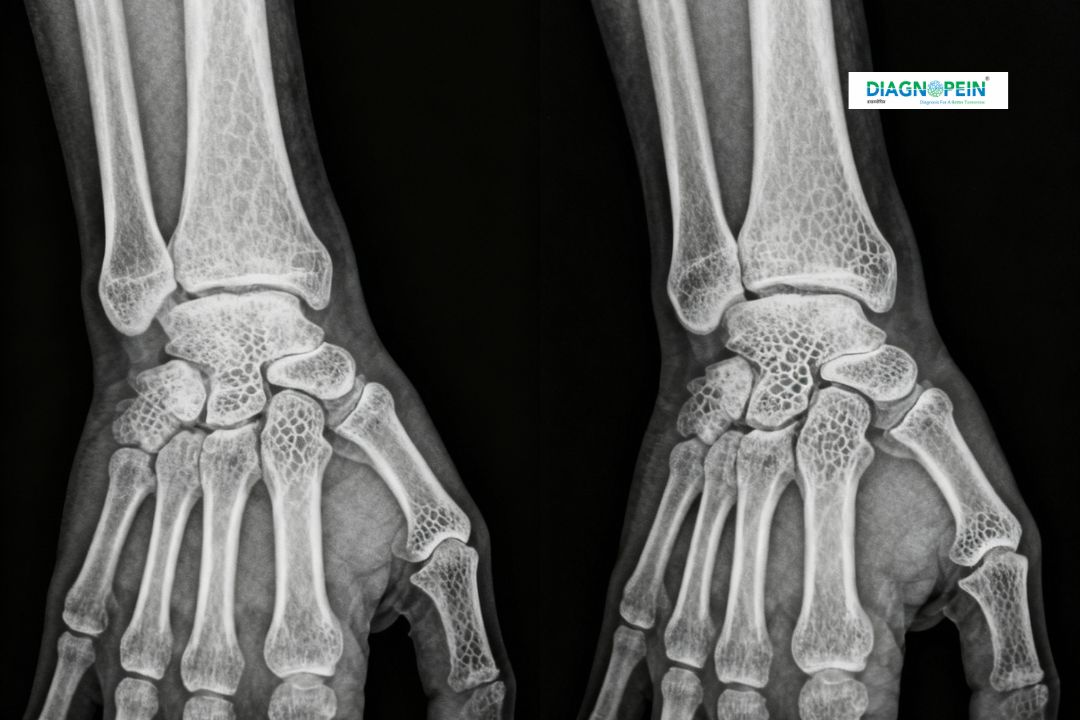

At Diagnopein Diagnostic Center in Karad, the X-Ray Both Wrist AP (Anteroposterior) View is a specialized imaging test used to examine both wrists simultaneously. It provides detailed images of the wrist bones, joints, and surrounding tissues. This helps doctors identify fractures, joint dislocations, degenerative changes, or early signs of bone diseases. Using advanced digital X-ray technology, our center ensures minimal radiation exposure and high-quality results for precise diagnosis.

X-rays are a quick, painless, and reliable way to assess wrist injuries or chronic conditions such as arthritis. The “AP View” refers to the image being taken from the front to the back of the wrist, helping radiologists see even subtle abnormalities clearly.

• Both wrists are positioned on the X-ray plate, palms facing upwards.

• The technician ensures correct positioning to capture a clear AP (front-to-back) image.

• A single exposure captures both wrists simultaneously.

The main parameters assessed in an X-Ray Both Wrist AP View include:

1. Bone alignment and joint spacing

2. Signs of fracture lines or bone fragmentation

3. Bone density patterns indicating metabolic or degenerative disease

4. Soft tissue swelling or calcification around the joints

5. Comparison of both wrists for symmetry and structural variation